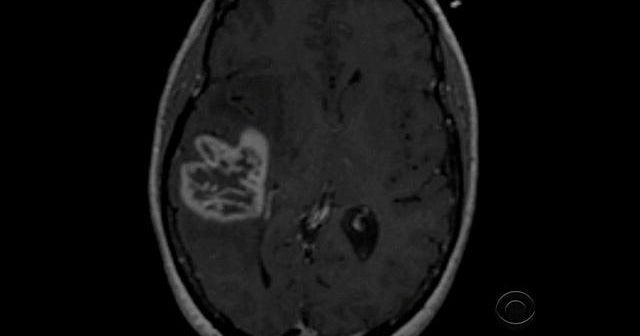

Duke University released a study Wednesday detailing the results of an experimental treatment aimed at getting a patient's immune system to fight off glioblastoma, a vicious form of brain cancer. The treatment, which incorporates a tetanus shot, has seen dramatic results in patients who were given just months to live. CBS News chief medical correspondent Dr. Jon LaPook reports.